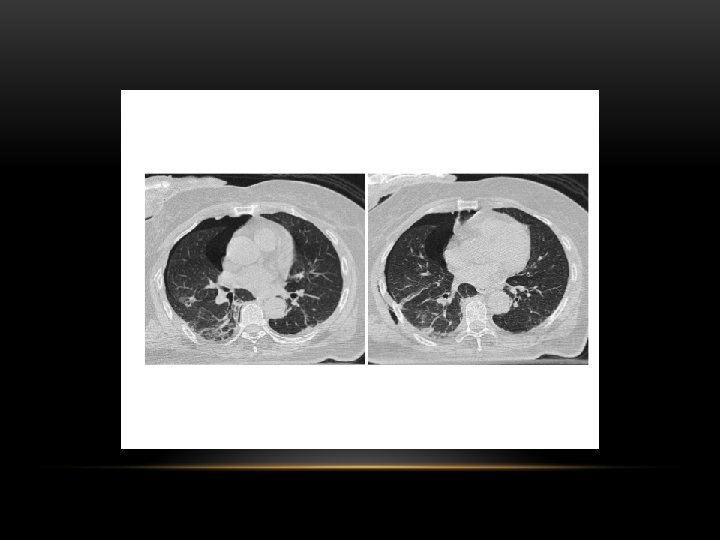

Pneumothorax is air in the pleural space. Radiological criteria: Air (black) in pleural space. No lung markings in pleural space. Recognition of atelectatic lung (lung margin). The lung recoils to a resting state as the negative pressure in the pleura is lost (relaxation atelectasis).

Shift of mediastinum to the opposite side. The mediastinum is held in the middle by balance between pleural pressures. When the negative pressure on the side of the pneumothorax is lost, the mediastinum gets pulled by the normal negative pressure from the opposite side. Progressive shift subsequently could result from a push secondary to tension pneumothorax. Opposite lung gets the entire cardiac output and the vascular markings become prominent.

Tension pneumothorax : is the progressive build-up of air within the pleural space, usually due to a lung laceration which allows air to escape into the pleural space but not to return. Positive pressure ventilation may exacerbate this 'one-way-valve' effect. Progressive build-up of pressure in the pleural space pushes the mediastinum to the opposite hemithorax, and obstructs venous return to the heart. This leads to circulatory instability and may result in traumatic arrest.

Spontaneous Pneumothorax • Air in pleural space • Lung margin • "Normal lungs": Note the radiolucency of atelectatic lung is the same as the opposite lung

Inspiratory Expiratory